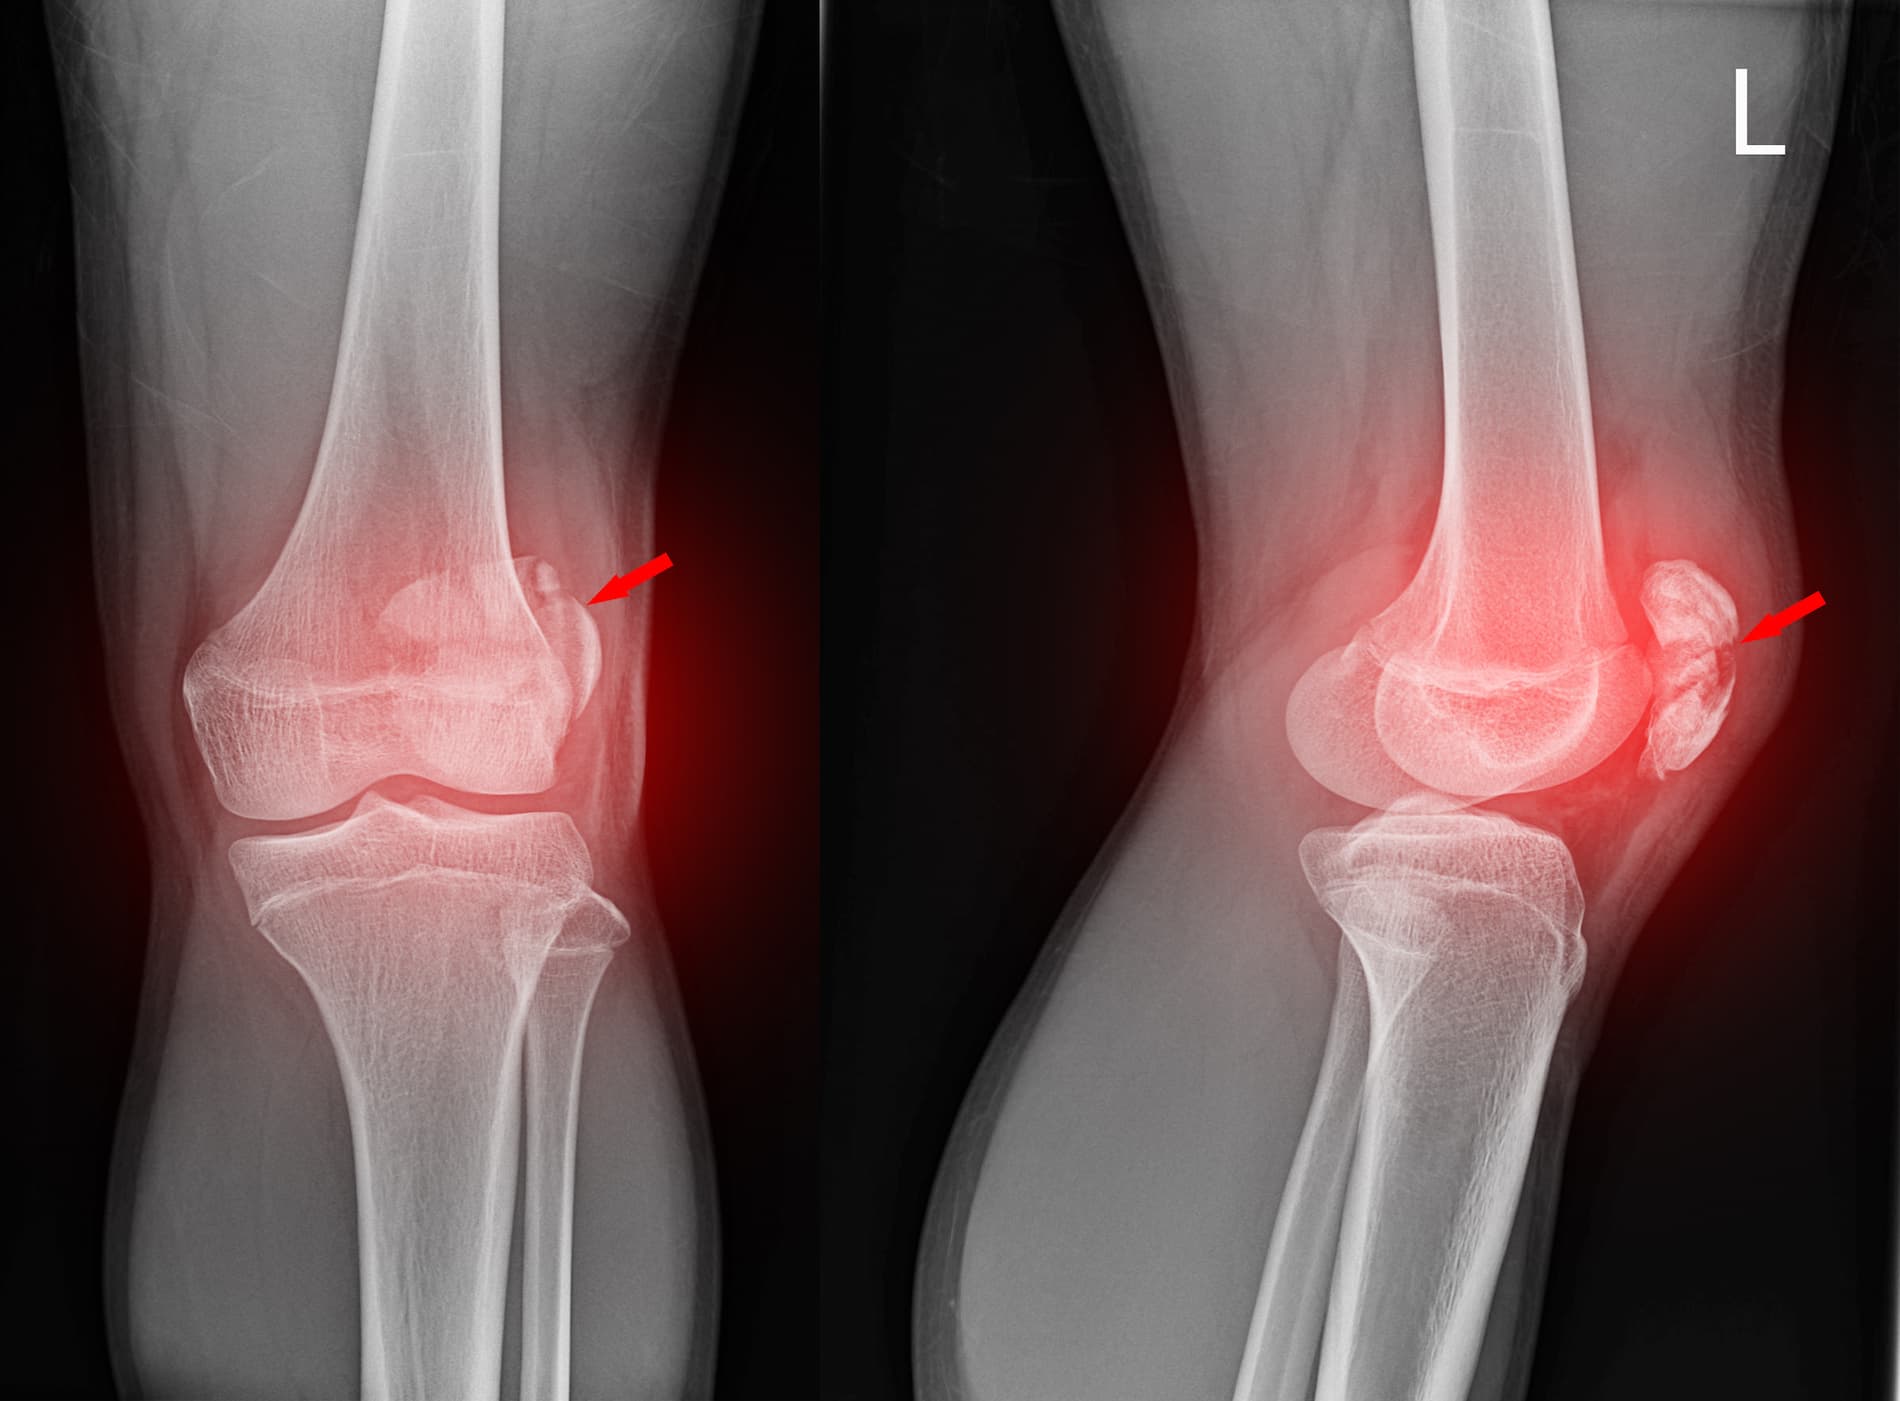

Arthroscopie du genou

L’arthroscopie du genou est une chirurgie mini-invasive permettant d’explorer et de traiter les lésions internes du genou.

Douleurs, blocages, lésions méniscales ou cartilagineuses.

Réalisée à l’aide d’une caméra, avec de petites incisions, elle permet une récupération rapide.

La reprise de la marche est souvent rapide, avec une rééducation adaptée selon le geste réalisé.

Méniscectomie arthroscopique

Il s’agit de retirer uniquement la partie abîmée du ménisque.

Suture méniscale

Cette intervention vise à réparer le ménisque plutôt qu’à le retirer.

Lésions méniscales chez des patients jeunes ou actifs, lorsque la réparation est possible.

La récupération est plus progressive qu’une méniscectomie, mais permet de préserver le genou à long terme.